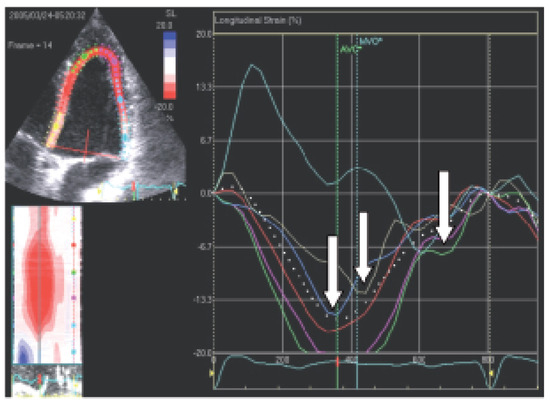

Biventricular pacing is an accepted therapy in patients suffering from terminal heart failure. Main obstacle however is the positioning of the left ventricular electrode via coronary sinus as well as its reliable fixation. This article describes in a...